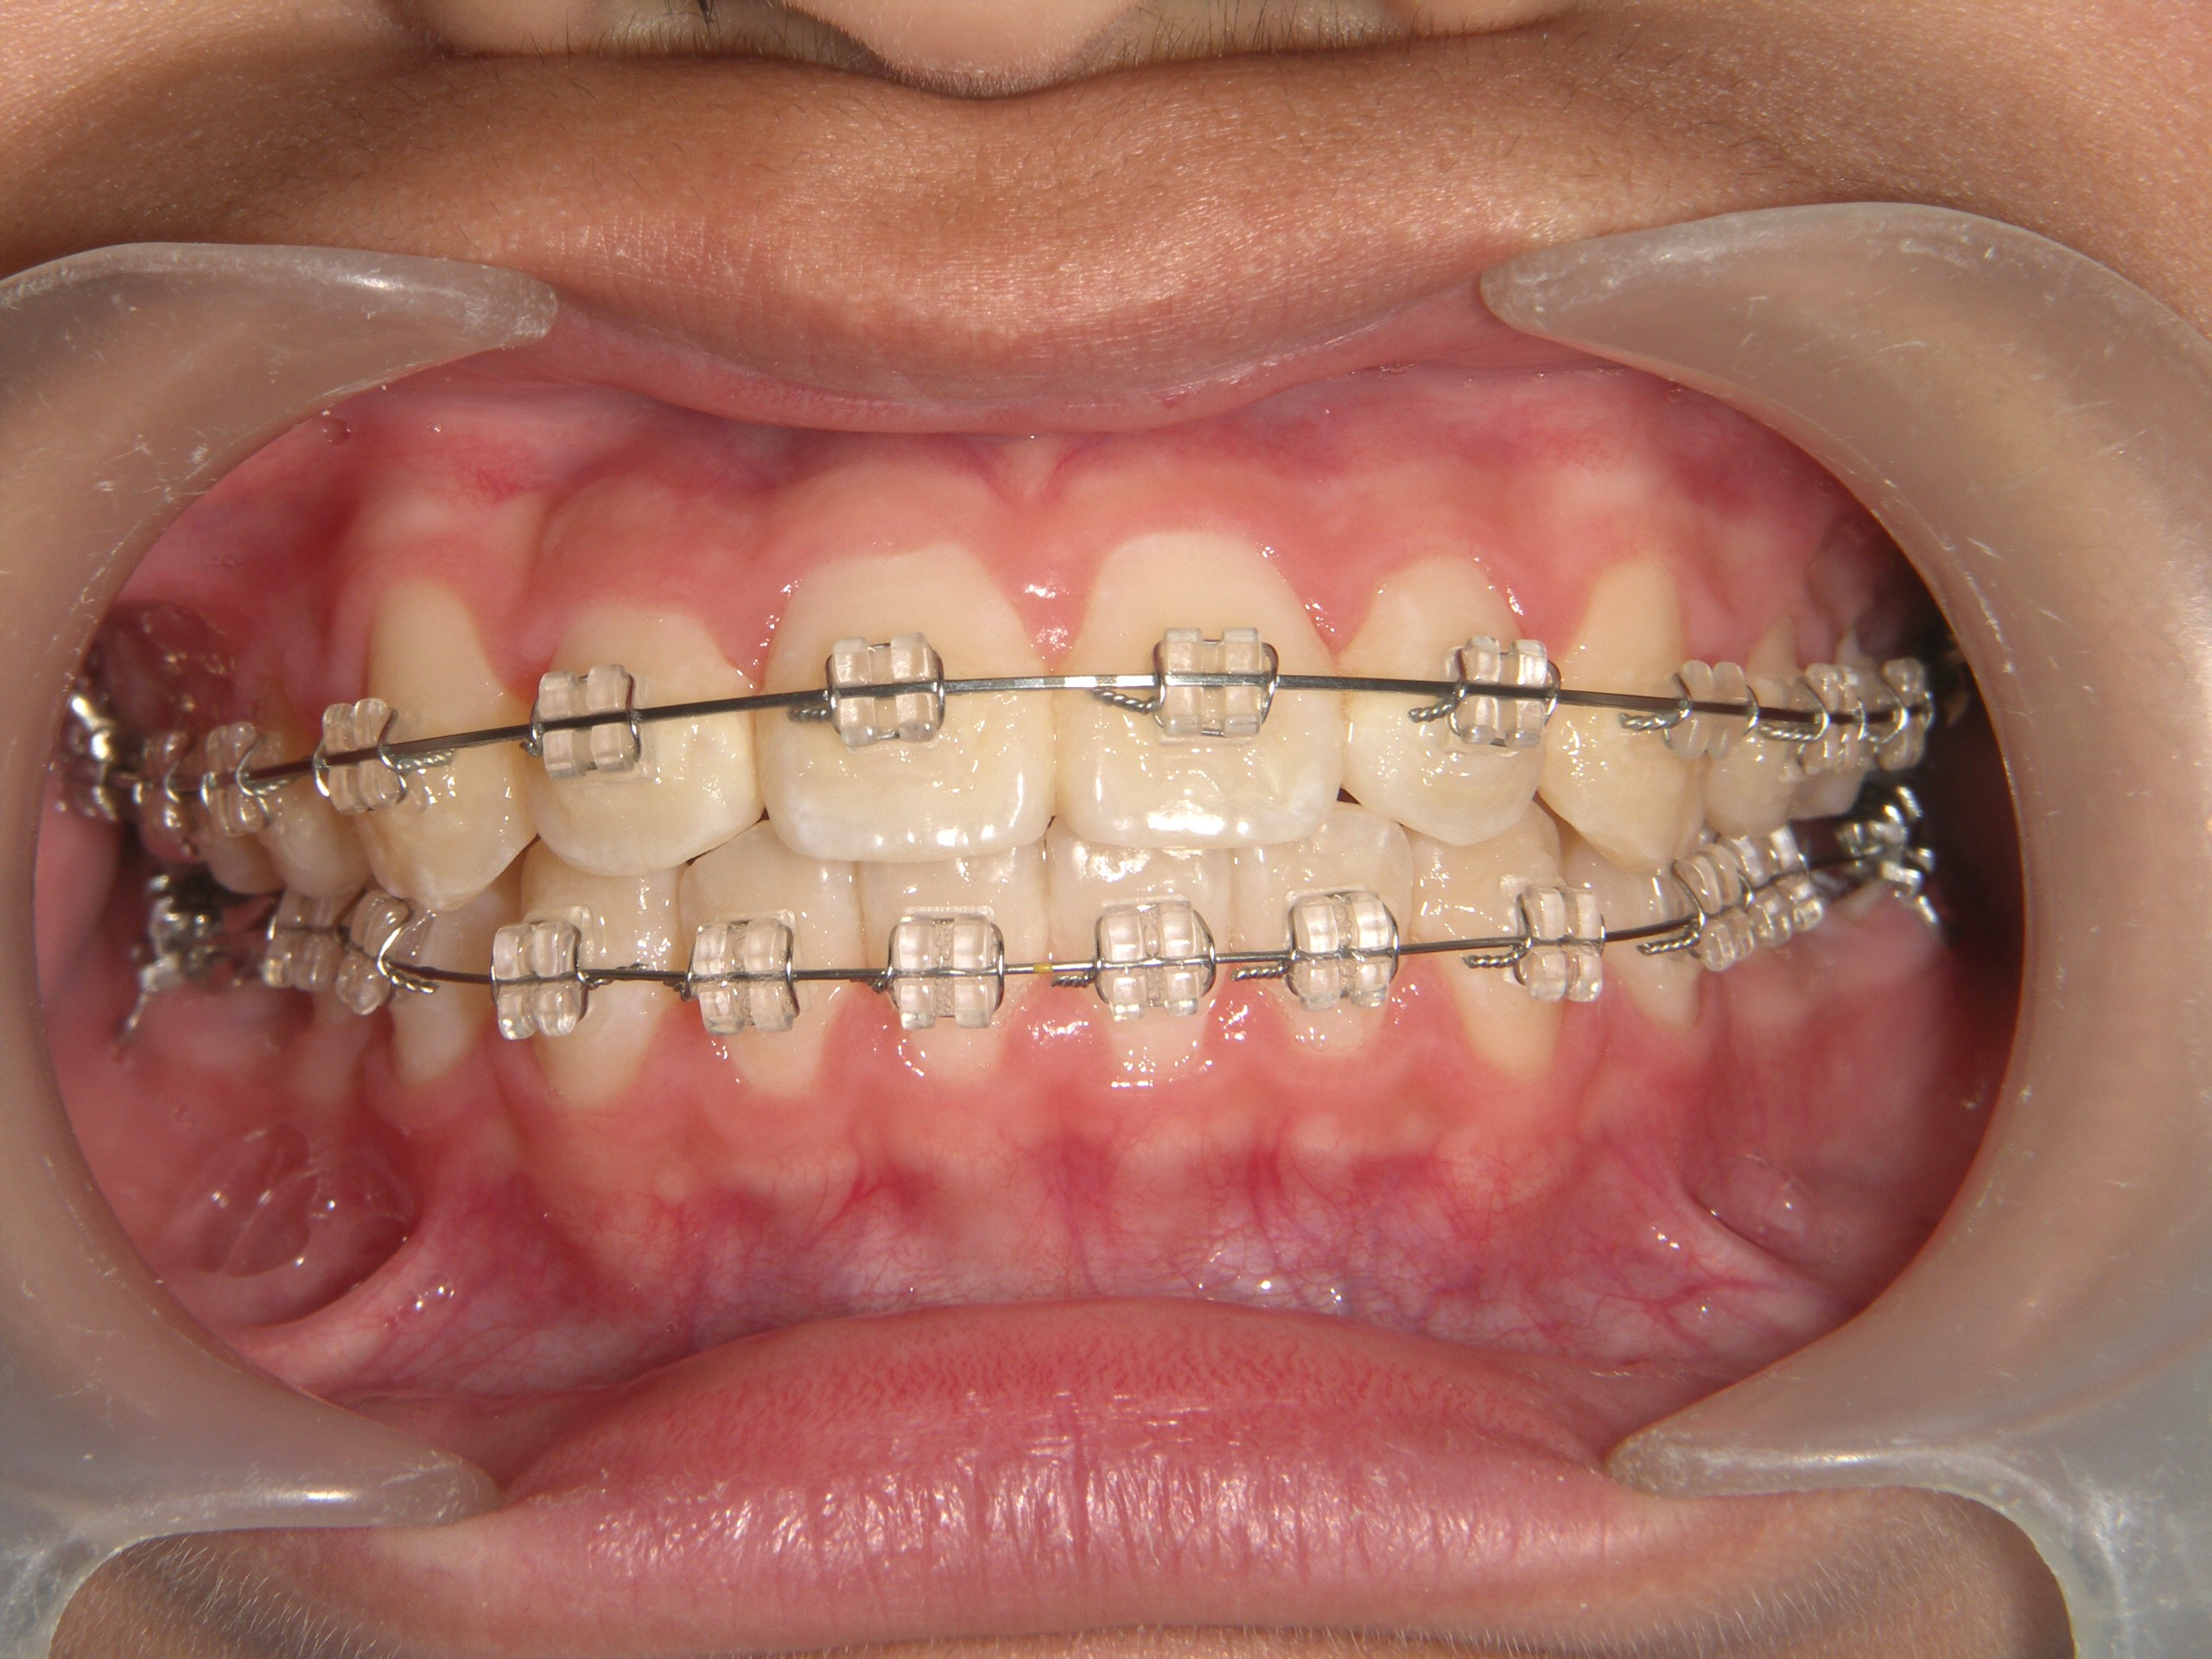

第2期治療開始時

口腔内写真

開始年齢

13歳

主訴(患者様のお悩み)

残りの歯のデコボコを治したい

診断

上下顎軽度の叢生(上下の歯のデコボコ)

上顎右側犬歯低位(右上の八重歯)

治療方針

非抜歯矯正治療

全体的に装置を装着し、歯のデコボコや咬み合わせを治療

使用装置

表側矯正装置

治療期間の目安:約1年~1年半(保定期間を除いた期間)

第2期治療終了時

治療結果

上下の歯のデコボコが改善

全体的な咬み合わせの緊密化